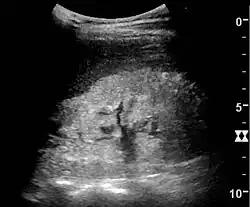

Ultrasound

Kidney ultrasonography is useful for diagnostic and prognostic purposes in chronic kidney disease. Whether the underlying pathologic change is glomerular sclerosis, tubular atrophy, interstitial fibrosis, or inflammation, the result is often increased echogenicity of the cortex. The echogenicity of the kidney should be related to the echogenicity of the liver or the spleen. Moreover, decreased kidney size and cortical thinning are often seen, especially when the disease progresses. However, kidney size correlates to height, and short persons tend to have small kidneys; thus, kidney size as the only parameter is unreliable.[63]

Nephrotic syndrome. Hyperechoic kidney without demarcation of cortex and medulla.[63] -